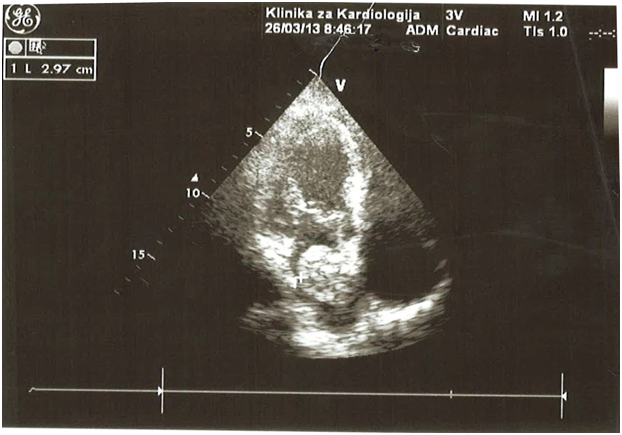

Transthoracic echocardiogram (Figure 2) (Figure 3) revealed a large atrial mass occupying the majority of the left atrium with dimensions 2,97 x 4,28cm with no obstruction of the mitral valve orifice. Transesophageal echocardiography (Figure 4) (Figure 5) confirmed presence of a large mass in the left atrium attached to the interatrial septum without prolaps of the tumour through the mitral valve. After coronary angiography and completion of preoperative dignostics, patient was transferred in another institution for surgical treatment. After surgical removal of the cardiac tumour, we received the histopathological material (Figure 6) which confirmed the diagnosis of cardiac myxoma. We continued with follow up of the patient by echocardiography control right after surgical treatment, as well as after 3 months, after 6 months, and after 12 months with no signs of tumor recurrence. She feels well and continues to take regularly antihypertensive drugs.7–9

Figure 2 TTE showing large mass attached to the atrial septum.

Figure 3 TTE showing large mass attached to the atrial septum (another position).